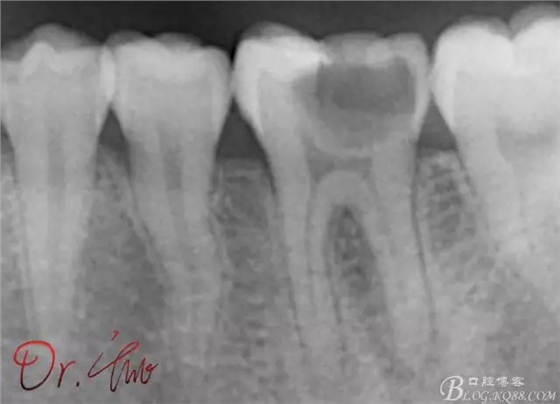

先來第一個病例

初診照